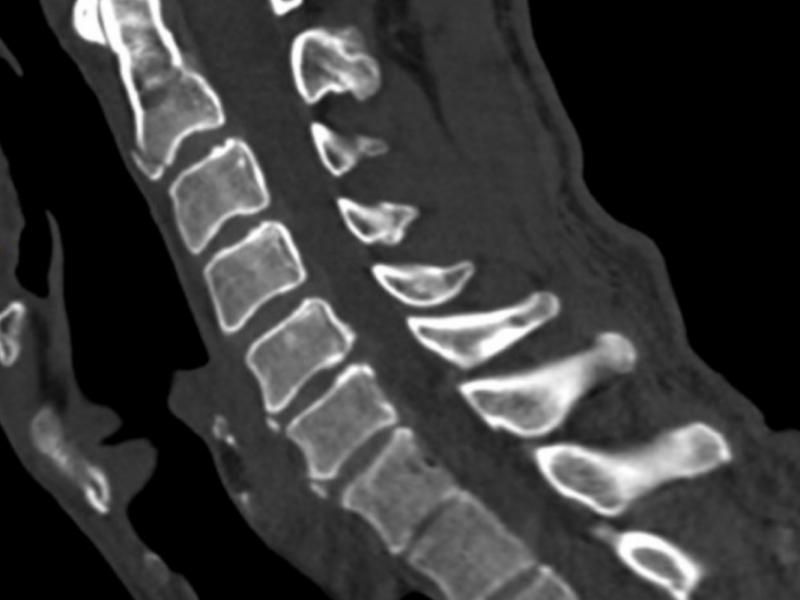

A 65 yo M presents to the ED after falling 10 feet off a